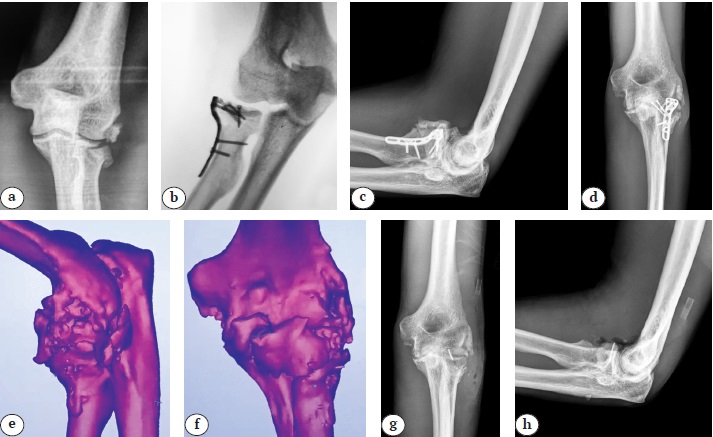

При краевых переломах типа Mason II предпочтительным вариантом остеосинтеза являлась фиксация отломков компрессионными винтами диаметром 2,0 и 2,4 мм. На рисунке 1 проиллюстрирован пример выполнения фиксации канюлированными винтами перелома ГЛК типа Mason II.

Рис. 1. Рентгенограммы локтевого сустава пациента с переломом головки лучевой кости типа Mason II после остеосинтеза компрессионными винтами : a, b — до операции; c, d — после операции; e, f — через 3 мес. после операции

Figure 1. Elbow X-rays of the patient with Mason type II radial head fracture after osteosynthesis with compression screws: a, b — before surgery; c, d — after surgery; e, f — 3 months after surgery